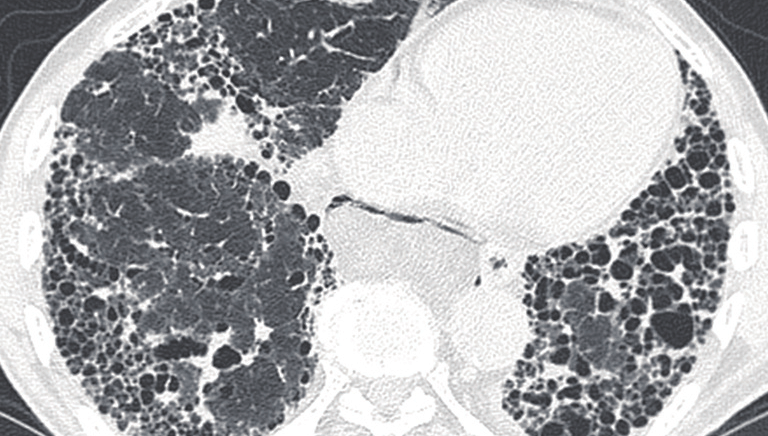

Następnie skierowałem swoje zainteresowania w kierunku pulmonologii – egzamin specjalizacyjny zdałem w 2012 roku pod kierownictwem Pana Profesora Dariusza Ziory w Klinice Chorób Płuc w Zabrzu, gdzie później pracowałem pogłębiając wiedze i doświadczenie szczególnie w diagnostyce i leczeniu chorób śródmiąższowych, co jest moim szczególnym zainteresowaniem.

Aktualnie kieruję dużym blisko 70 łóżkowym oddziałem chorób płuc i gruźlicy w pilchowickim Szpitalu Chorób Płuc. Zajmuję się endoskopową ( bronchoskopia, EBUS) diagnostyka chorób płuc, w tym nowotworowych. Diagnostyką śródmiąższowego włóknienia płuc i kwalifikacją do leczenia w ramach programu lekowego – IPF w naszym oddziale. Od ponad 15 lat prowadzę poradnie domowego leczenia tlenem stąd zajmuję się oceną i kwalifikacja chorych do leczenia tlenem w domu.

Choroby śródmiąższowe

Opieka nad pacjentami z włóknieniem płuc i sarkoidozą